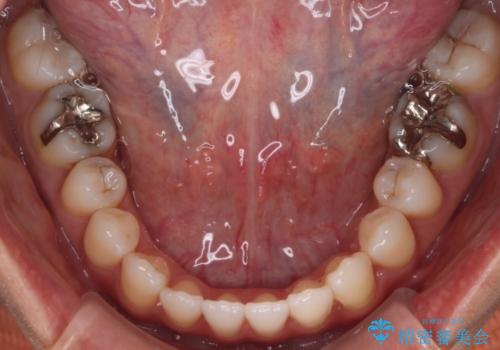

- 開咬を主訴に来院されました。前歯部に開咬、右側大臼歯部にクロスバイトが認められます。ワイヤー矯正の審美装置で治療し、ゴム掛けを行いながら噛み合わせを改善しました。

主訴である開咬と右側大臼歯部クロスバイトを改善でき、しっかりと噛むことができるようになりました。